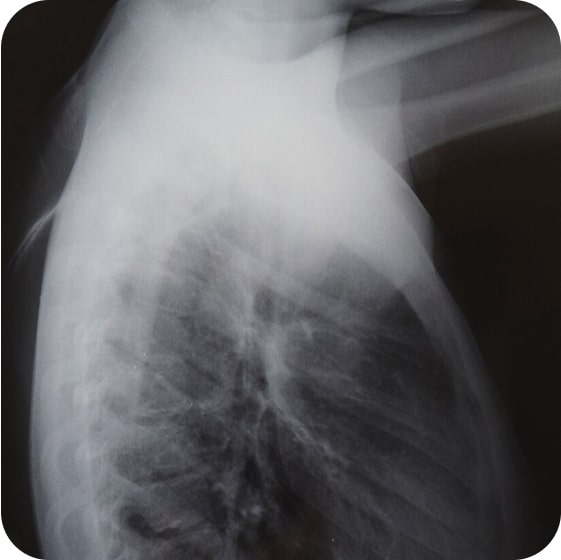

Определить болезнь можно с помощью рентгенографии или компьютерной томографии легких. На снимке будет видно, поражен ли орган.

Рентгенографическое исследование легких

С его помощью можно выявить новообразования и очаги воспалительных процессов.